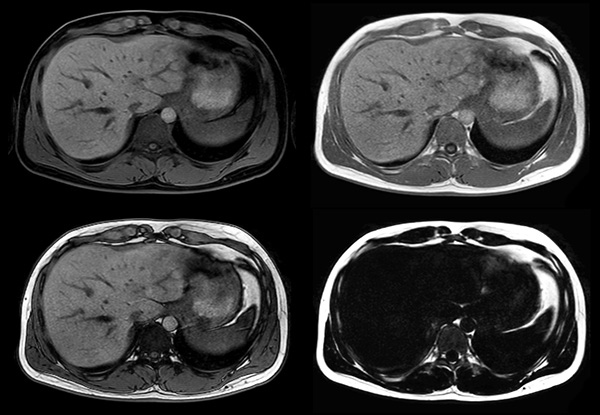

Axial mDIXON (W, IP, OP, F)